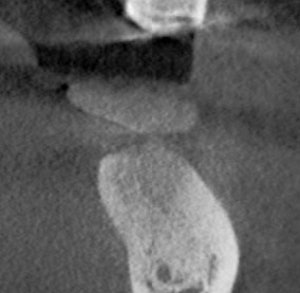

On review of his 3D images, it became apparent that neglecting to intervene earlier had allowed periodontal hard-tissue breakdown to progress to an unmanageable state for tooth #3 and possibly for tooth #14. Tooth #19 was deemed hopeless and could be extracted, bone grafted, implanted, and restored, as the bone volume could be regenerated to receive an implant.

The incidental findings in this scan were multiple: the total resorption of palatal bone in the area of tooth #14 with periapical pathology, and the complete destruction of alveolar support for tooth #3, which was close to undermining the apices of the adjacent premolar #4. The treatment plan was formulated based the images shown.